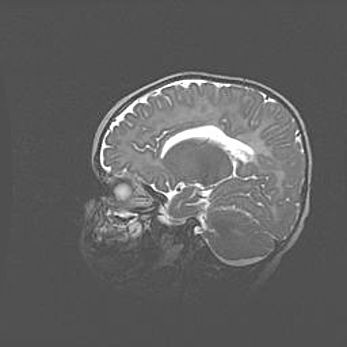

Аномалия Денди-Уокера. Признаки гипоплазии мозолистого тела.

Возраст: 5 месяцев 3 дня

Вес: 5550 г

Пол: мужской

Окружность головы: 39 см

Срок гестации: 40 недель

Аномалия Денди-Уокера – это порок развития головного мозга, для которого характерна триада симптомов: гипотрофия или аплазия червя мозжечка и/или полушарий мозжечка, расширение четвёртого желудочка с формированием ликворной кисты задней черепной ямки, гипертензионная гидроцефалия различной степени.

Гипоплазия мозолистого тела относится к дефектам внутриутробного этапа развития мозговой ткани, возникающим в процессе закладки структур головного мозга, что происходит на начальных этапах развития эмбриона.